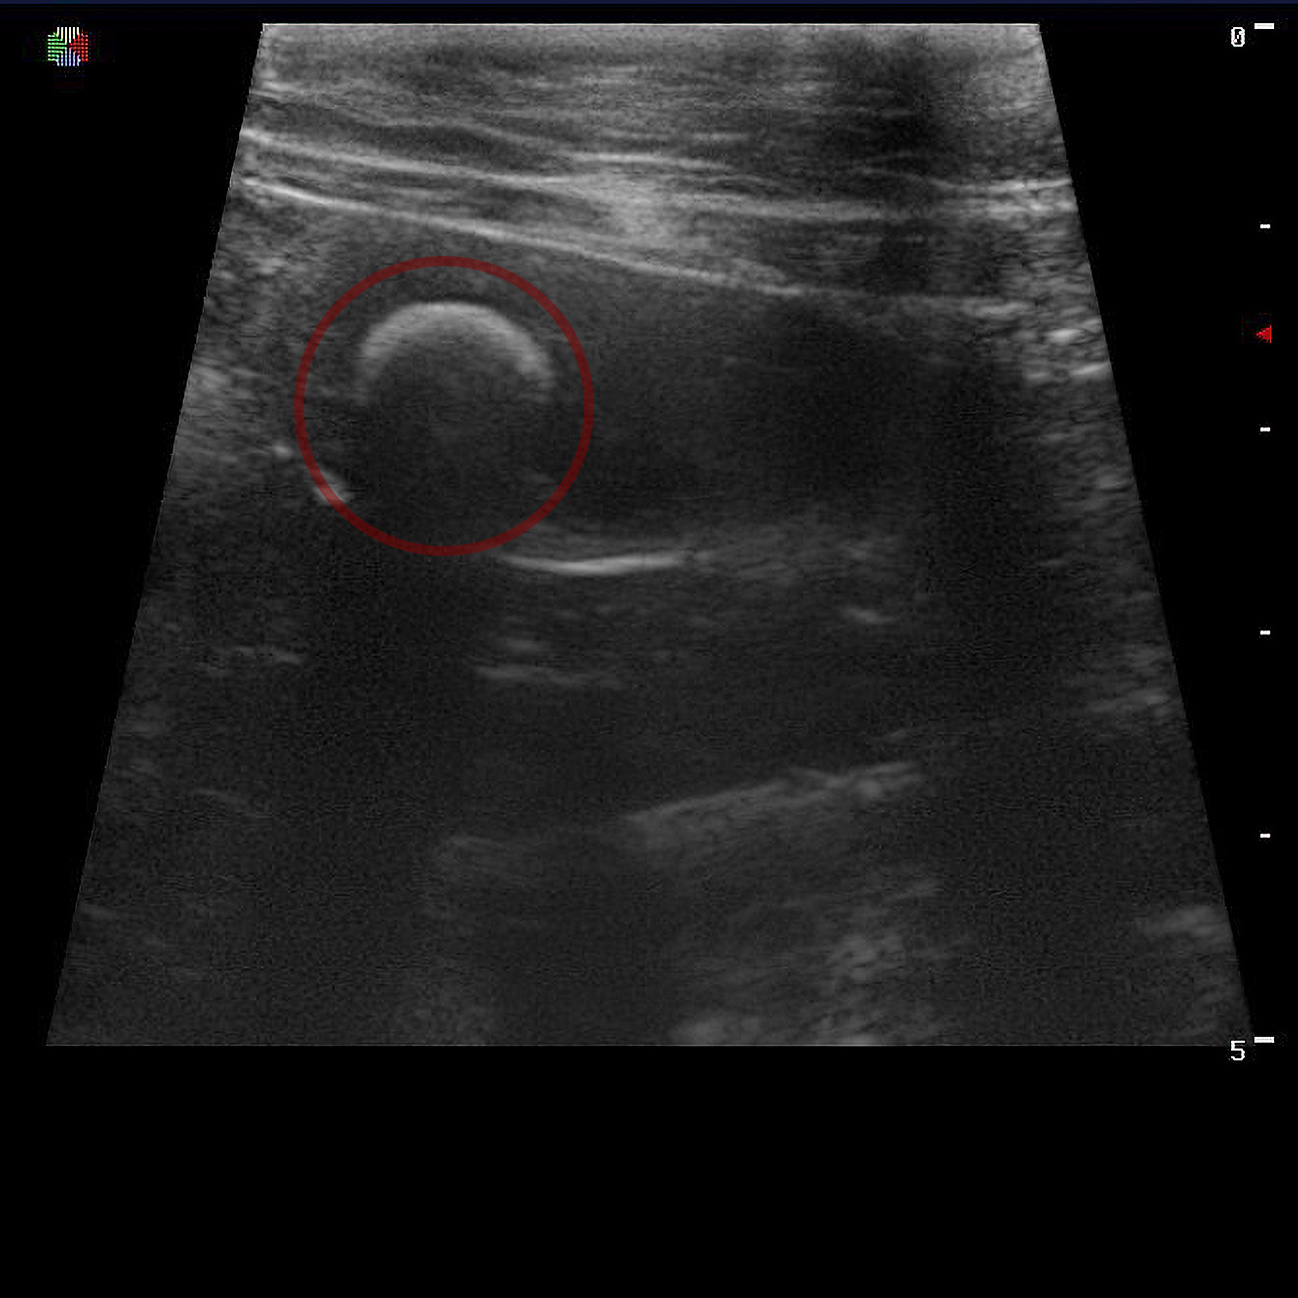

Визуализация камня с помощью УЗ-диагностики